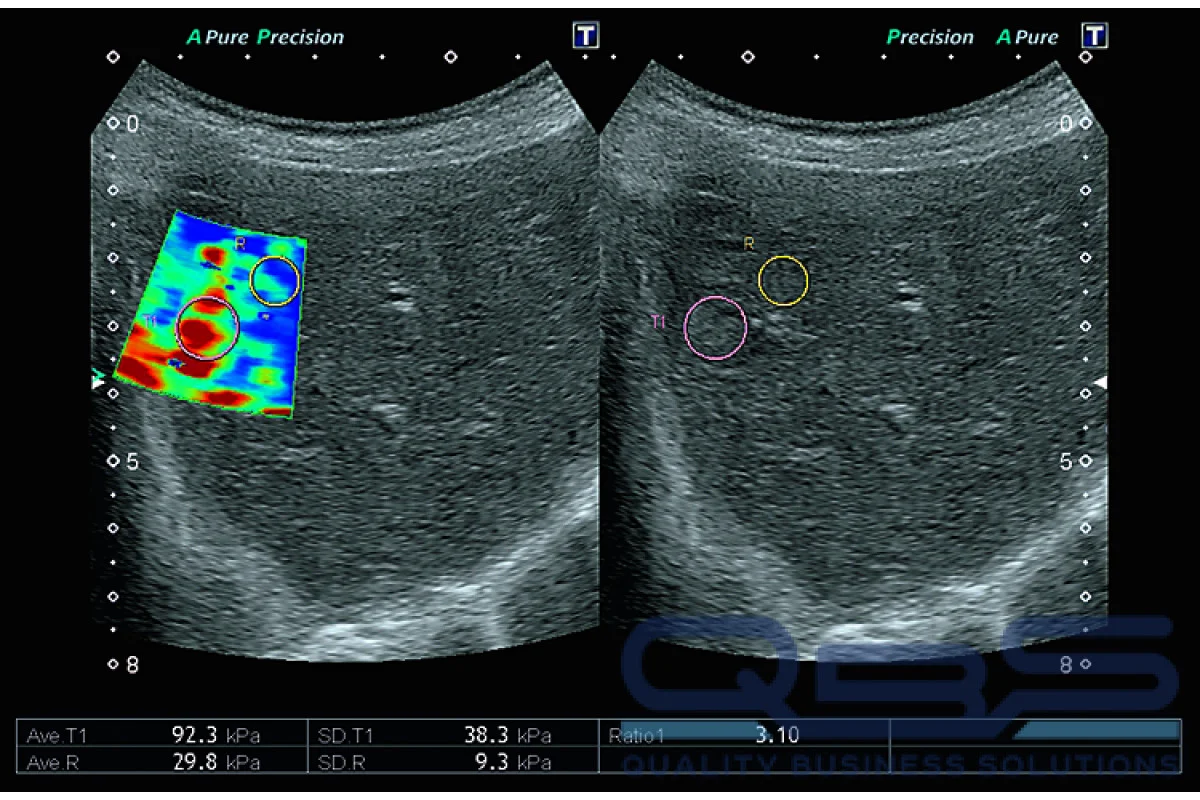

• Periodic FibroScan tests to track the stability or regression of scar tissue.

• Advanced Technology: We use the latest diagnostic imaging and non invasive stiffness testing.